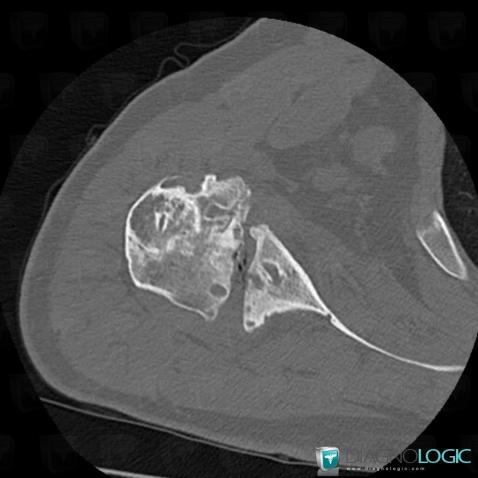

Degenerative joint disease, Humerus - Proximal part, Gleno humeral joint, CT

Here is the specific information in the key image above:

- Diagnosis Degenerative joint disease, Location(s) Gleno humeral joint, with gamuts Arthritis without osteoporosis, Monoarticular joint diseaseHumerus - Proximal part, with gamuts Epiphyseal osteolysis